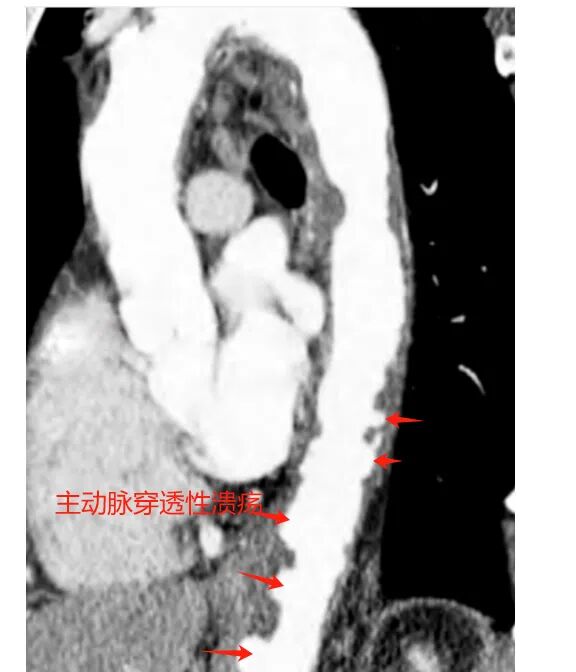

主动脉管壁由三层结构组成,内膜、中膜、外膜。当主动脉内膜粥样硬化斑块破裂,穿透内膜侵及中膜,脱落后呈溃疡样改变,称为主动脉穿透性溃疡(PAU)。

主动脉穿透性溃疡

主动脉溃疡确诊主要依靠主动脉增强CT,普通CT难以确诊。

增强CT显示主动脉局限性节段扩张,局部溃疡形成,壁内可见血肿。